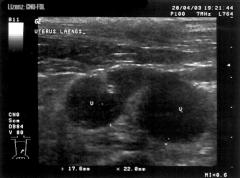

Glandulär-zystische Hyperplasie des Endometriums

Die Glandulär-zystische Hyperplasie des Endometriums ist eine krankhafte Verdickung (Hyperplasie) des Endometriums (der Schleimhaut der Gebärmutter), die aufgrund der Besonderheiten im Sexualzyklus besonders bei Hunden auftritt. Sie kann als Vorstufe einer echten Endometritis bzw. Pyometra (Gebärmuttervereiterung) angesehen werden und wird daher dem Endometritis-Pyometra-Komplex zugeordnet.

Die Erkrankung verläuft weitgehend ohne Symptome und ähnelt einer chronischen Gebärmutterschleimhautentzündung.

Eventuell kann ein Ausfluss aus der Vagina auftreten und aufgrund der verlängerten Östrogenwirkung eine anhaltende Attraktivität für Rüden. Bei Meerschweinchen äußert sich die Krankheit in mit dem Harnabsatz auftretenden Blutbeimengungen.

Pathologisch-anatomisch sind die Gebärmutterhörner verdickt (1 bis 3 cm) und es finden sich 1 bis 7 mm große Zysten.

Die häufigste Komplikation ist die Entstehung einer Pyometra. Da hohe Östrogenspiegel auch zu Schädigungen des Knochenmarks führen können, ist das Auftreten einer Anämie, Thrombozytopenie oder Leukopenie möglich.